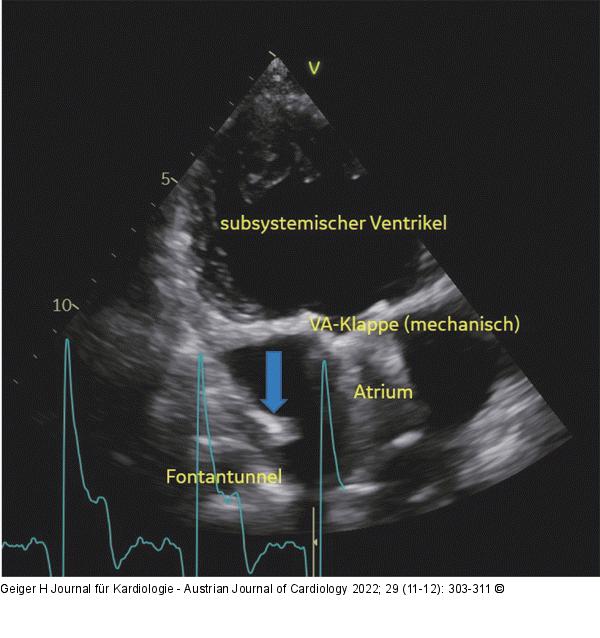

Abbildung 10: Single Ventricle Single Ventricle. Die atrioventrikuläre (AV-) Klappe zwischen Vorhöfen und Ventrikel (im Bild fälschlich als VA-Klappe bezeichnet) ist eine mechanische Prothese. Links unten sieht man den Fontan-Tunnel mit einer hyperechogenen Struktur, die in den Vorhof ragt (blauer Pfeil). Das ist der Schirm, mit dem die nach der Fontan-Operation belassene kleine Fenestration verschlossen wurde. |

Single Ventricle. Die atrioventrikuläre (AV-) Klappe zwischen Vorhöfen und Ventrikel (im Bild fälschlich als VA-Klappe bezeichnet) ist eine mechanische Prothese. Links unten sieht man den Fontan-Tunnel mit einer hyperechogenen Struktur, die in den Vorhof ragt (blauer Pfeil). Das ist der Schirm, mit dem die nach der Fontan-Operation belassene kleine Fenestration verschlossen wurde. |